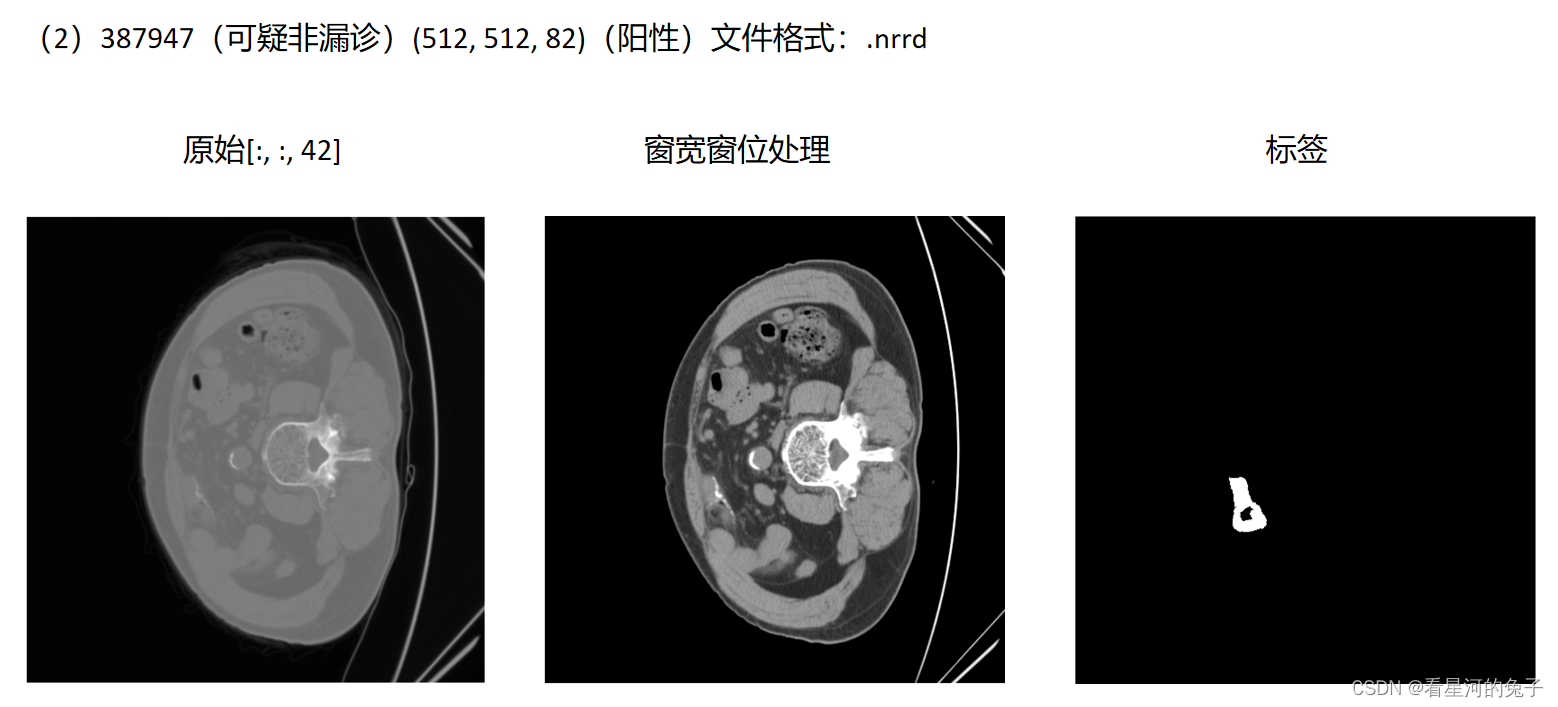

结果展示